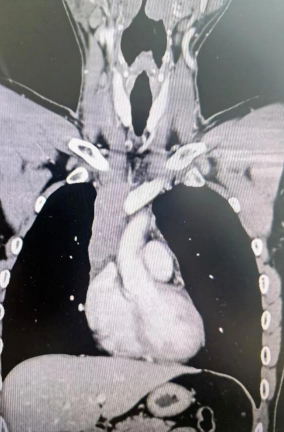

經(jīng)檢查發(fā)現(xiàn)患者前上縱隔腫瘤已經(jīng)完全侵犯了我們?nèi)梭w最主要的大靜脈之一——上腔靜脈,導(dǎo)致上腔靜脈回流嚴(yán)重受阻并導(dǎo)致由上腔靜脈起至左側(cè)無(wú)名靜脈、右側(cè)鎖骨下靜脈、右側(cè)頸內(nèi)靜脈等多根自上往下回流的靜脈阻塞,從而形成了廣泛的栓子,牢牢堵住了要流回心臟的血流,只能靠別的一些側(cè)支循環(huán)超負(fù)荷的工作,這也就是為什么孫先生脖子甚至是頭都明顯腫起來(lái)的原因。

術(shù)后患者經(jīng)過(guò)心外監(jiān)護(hù)室和胸外監(jiān)護(hù)室的接力治療,目前患者恢復(fù)順利,顏面部腫消失。復(fù)查增強(qiáng)CT三條人工血管通暢。